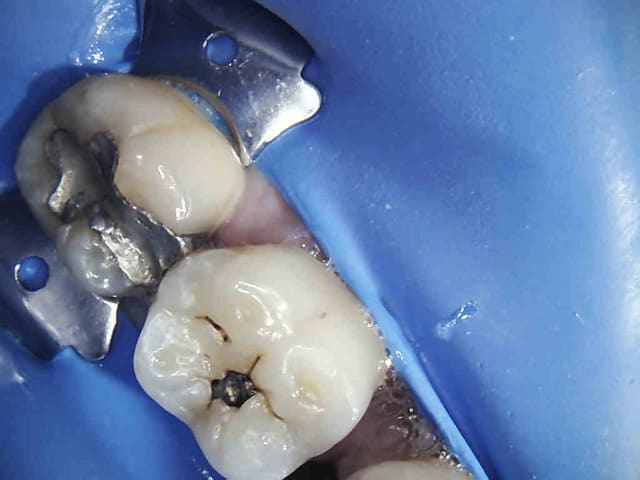

nic Tone en action ;)

Par exemple :